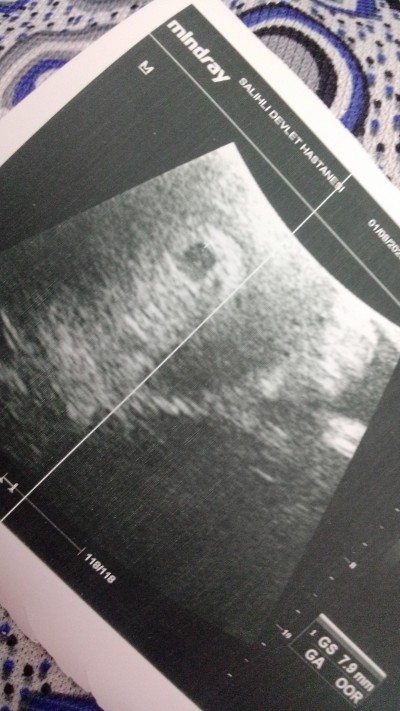

Merhaba annişler ❤️ Ben geçen hafta cuma günü öğrendim gebe olduğunu testte ve kan tahlilinde 1000.0ml ckmsti.ama ultrasonda kese yoktu. Pazartsi tekrar kan tahlili verdim betahcg 5754 ckti. Tekrar baktı ultrasondan kese göründü ama bebek henüz küçükmüş kaç haftalık olduğumu solemedi doktor bende okdr soru sordum ki unuttum. Tekrar ertesi gün kan verip bütün sonuçlarını aldı idrar filan 10 gün sonra gel kalp atışını dinlersin dedi dış gebelik yok dedi sizce 10gn içinde kalp atışı olurmu ilk gebeliğim acemiyim streste yapıyorum çok ☺️kaç haftalık tam ozmn son adet tarihim 19haziran. Bilgisi olan yazabilirimi  Teşekkür ederim

Gebelik haftası 6+1